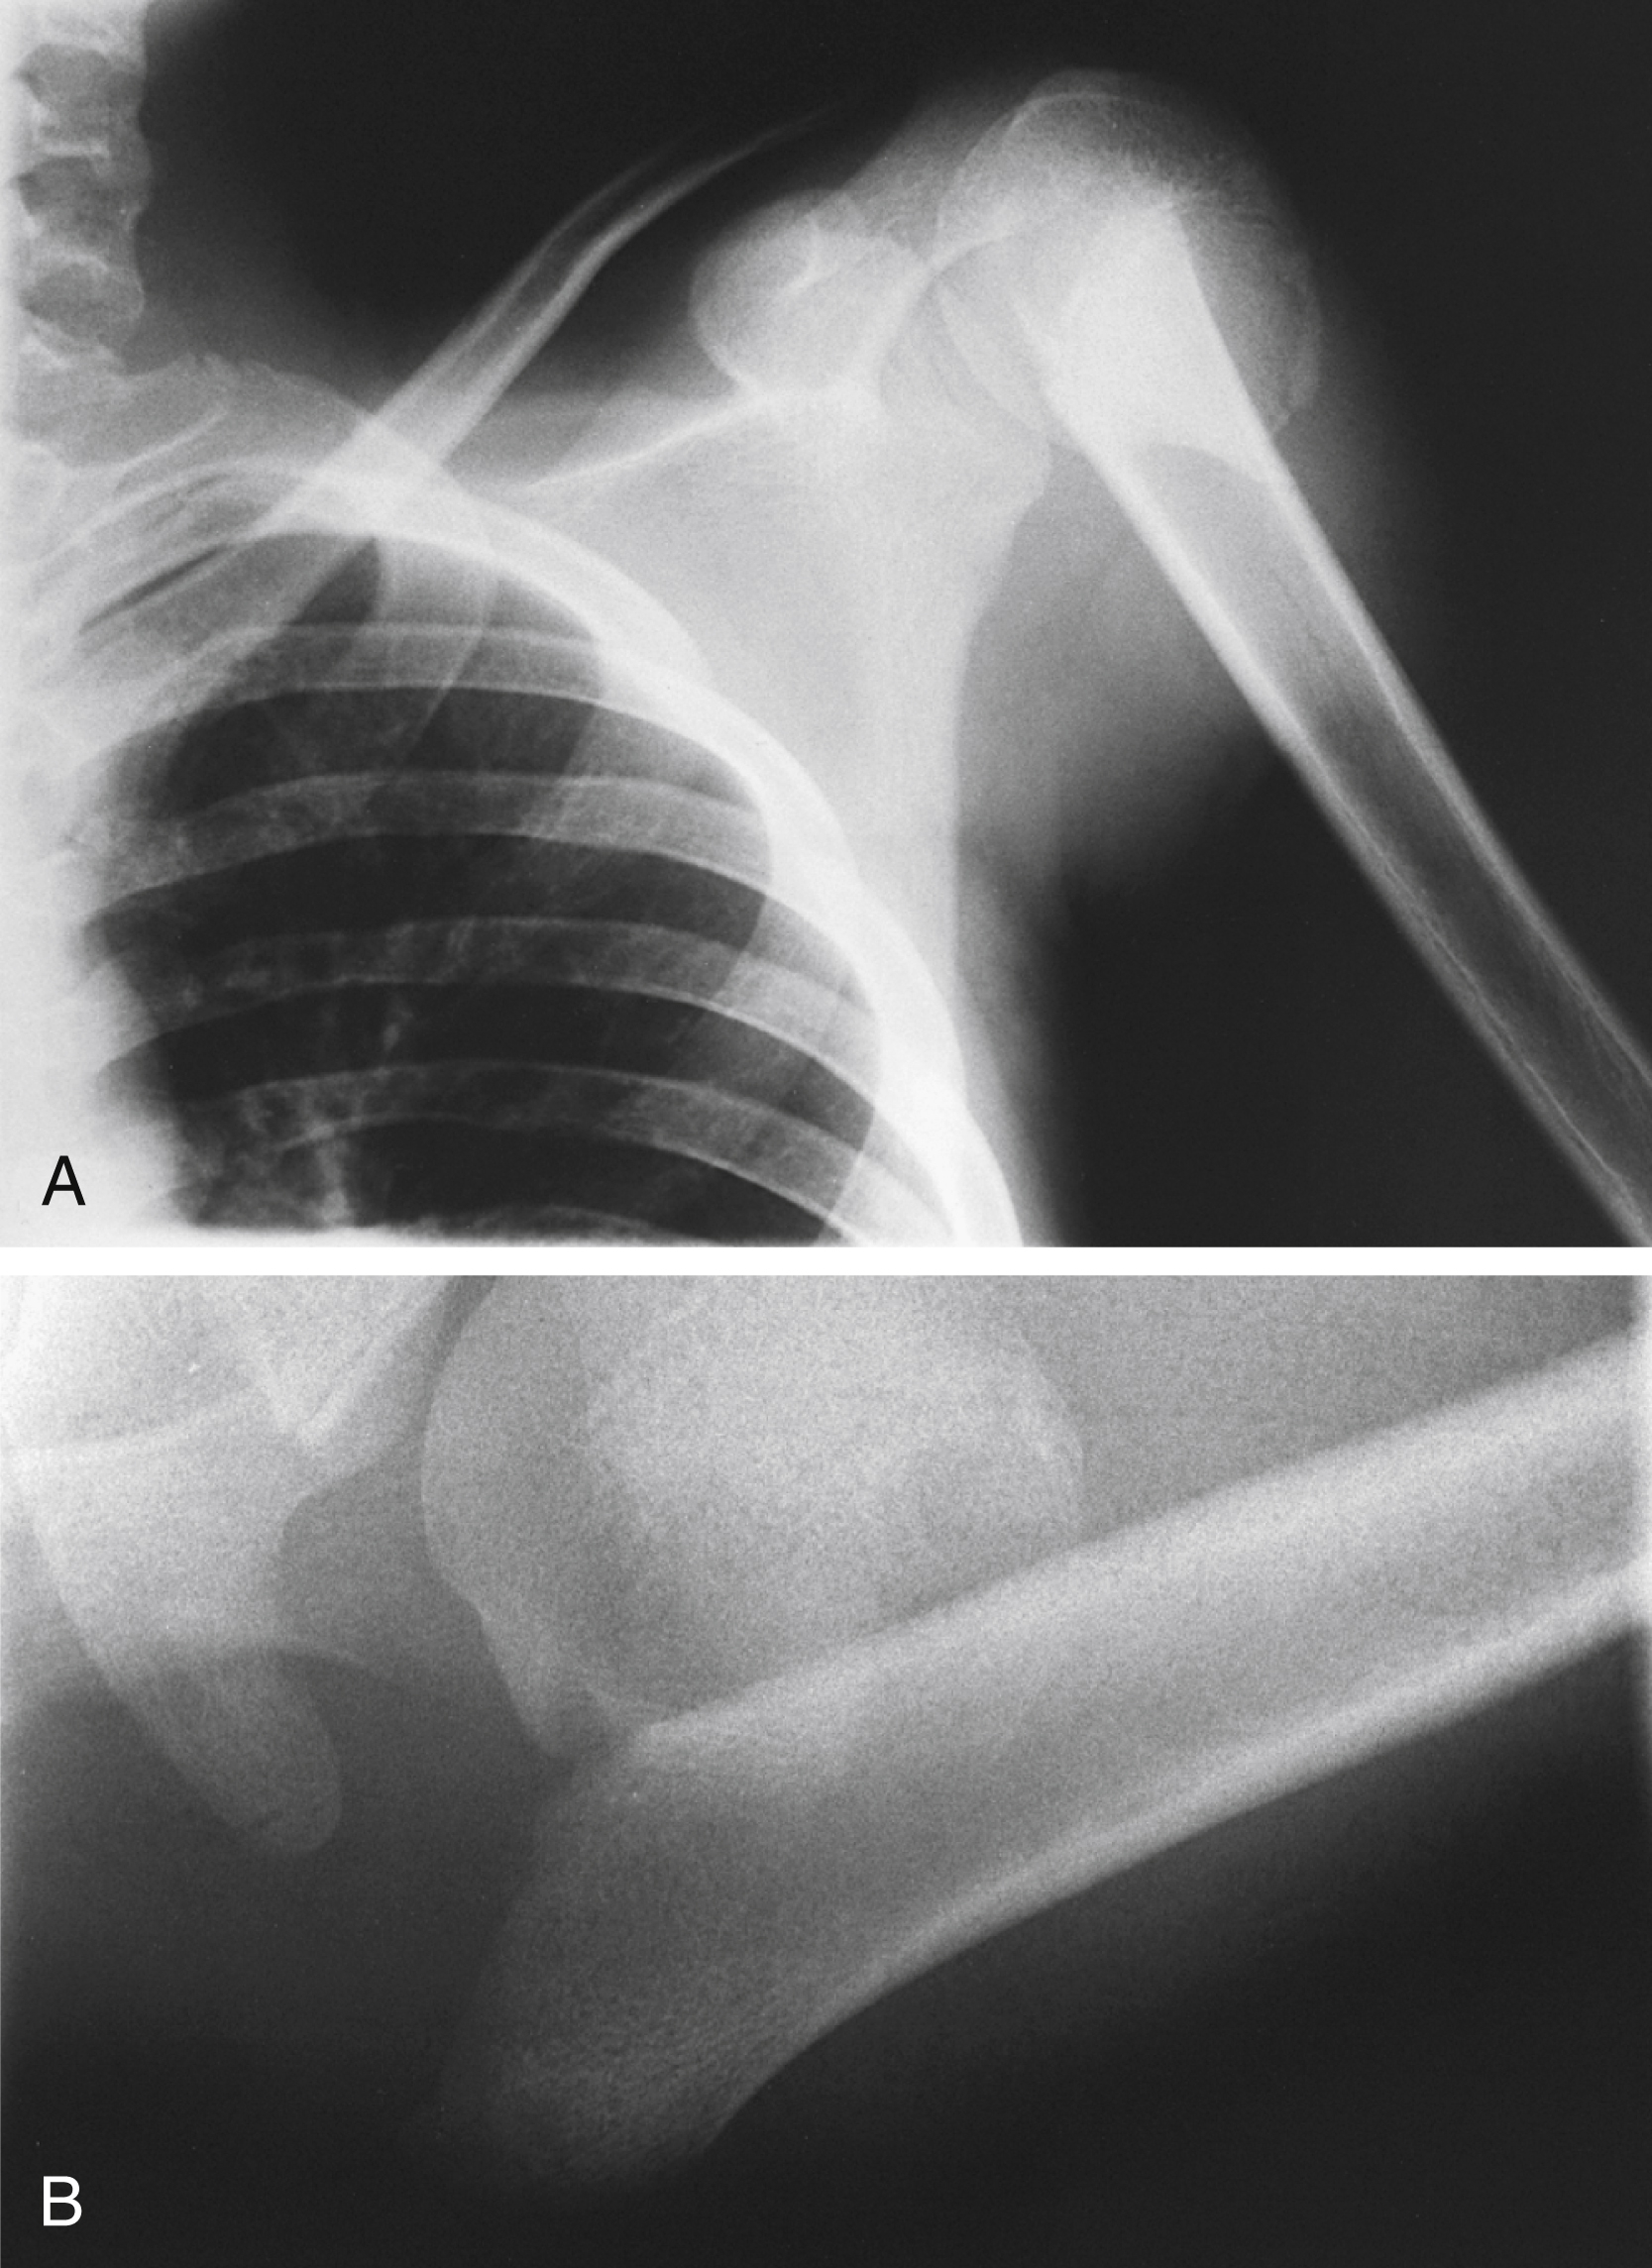

Fractures of the proximal humerus separate along old epiphyseal lines, producing four distinct segments consisting of the articular surface (anatomic neck), greater tuberosity, lesser tuberosity, and humeral shaft (surgical neck). The Neer classification system is based on the relationship of these fracture fragments. In this system, a segment is considered displaced if it is angled more than 45 degrees or separated more than 1 cm from the neighboring segment. Because this classification system considers only displacement, the number of fracture lines is irrelevant. There are four major categories of fracture: (1) minimal displacement ( Fig. 45.12 ), (2) two-part displacement ( Fig. 45.13 ), (3) three-part displacement, and (4) four-part displacement. When present, anterior and posterior dislocations are included as part of the classification. Impaction and head-splitting fractures are classified separately.

Three-part minimally displaced fracture of the proximal humerus involving the greater and lesser tuberosities.

Anteroposterior (A) and axillary (B) radiographic views of a two-part displaced fracture of the proximal humerus. The degree of displacement often is better visualized on the axillary view.

Courtesy David Nelson, MD.